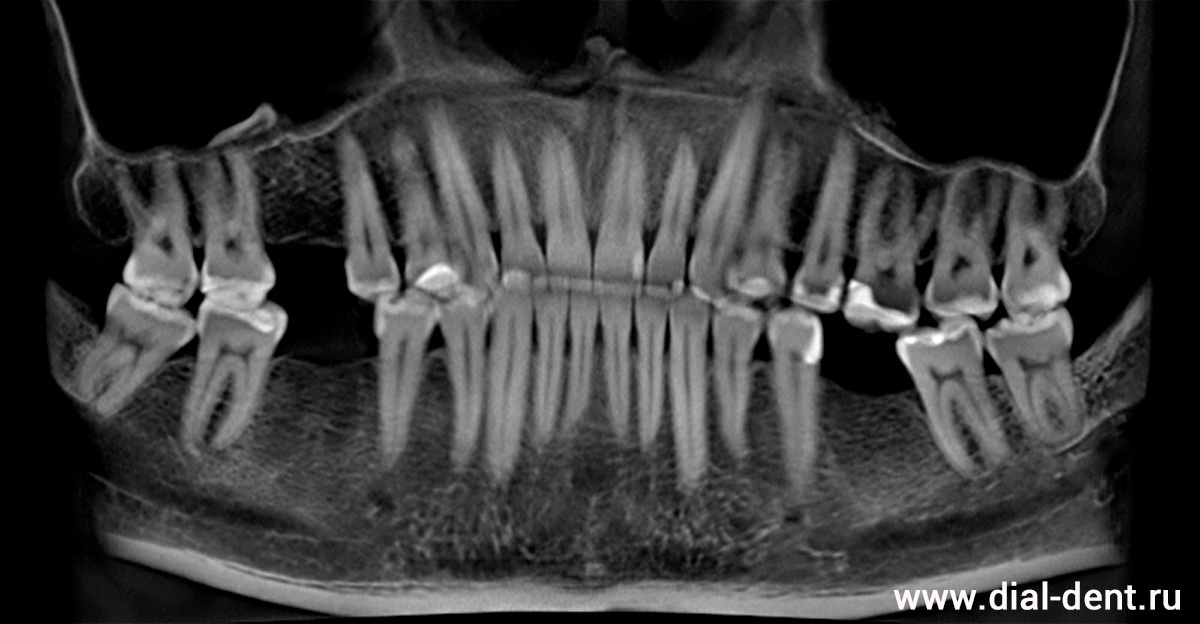

панорамный снимок зубов до лечения - три зуба отсутствуют

Молодой мужчина, обратился в Семейный стоматологический центр "Диал-Дент" по совету знакомых, чтобы восстановить три зуба, недавно удаленных из-за сильного разрушения. Так как сделал он это вовремя, никакой ортодонтической подготовки (например, перемещения соседних зубов) не потребовалось. Прикус в целом удовлетворительный, зубы не стерты. Можно просто установить импланты и коронки на импланты, и пациент получит полноценную улыбку.

План лечения составлен после консультации у хирурга-имплантолога. Небольшое осложнение в данном случае составило то, что при удалении зубов (в другой клинике) не учли последующую имплантацию, поэтому есть дефицит костной ткани и десны. Но это легко решается за счет добавления костного материала и пластики десны, которые будут сделаны в одну операцию с установкой имплантов. А чтобы молодой человек сильно не нервничал (а он очень боялся хирургии), установка имплантов и другие процедуры будут выполнены в седации. В седации пациент как-бы спит, после операции ничего не помнит, поэтому все проходит спокойно, без стресса.